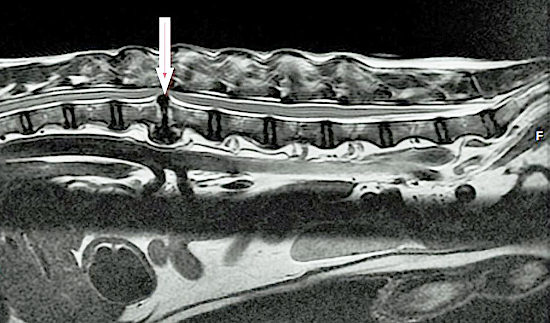

La paralysie se définit comme la perte de motricité et de sensibilité d’un ou de plusieurs muscles. Si Elle résulte le plus souvent de lésions neurologiques, ses origines sont multiples: mécanique (hernie discale, luxation), vasculaire (thrombo-embolie), métabolique, néoplasique ou infectieuse. Elle peut enfin être consécutive à un choc ou à un traumatisme (chute, accident de la voie publique, etc).

On parle de tétraplégie Lorsque la paralysie touche les membres supérieurs et inférieurs. Lorsque seules les pattes arrière sont touchées, il s’agit de paraplégie.